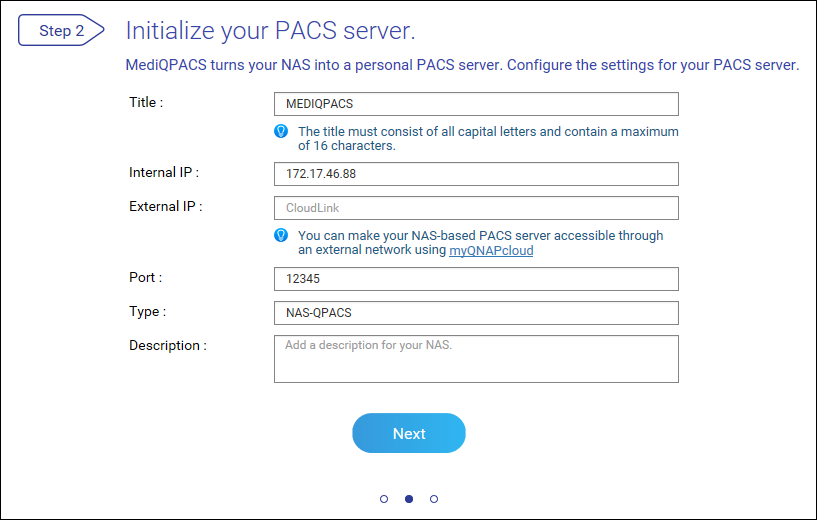

将 NAS 设置为 PACS 服务器

首次登录后,MediQPACS 管理员必须将 NAS 初始化为 PACS 服务器。

应用实体 (AE) 管理

在 DICOM 中,应用实体 (AE) 表示 DICOM 网络中的端点系统或程序,例如设备或 PACS 服务器。将 NAS 配置为 PACS 服务器时,将它视为一种 AE。